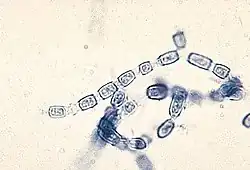

Artrokonidium, artrospora (łac. arthroconidium, l.mn. arthroconidia) – zarodnik konidialny u grzybów powstający w ten sposób, że w niektórych komórkach strzępek następuje pogrubienie ściany komórkowej, a następnie sąsiednie komórki rozpadają się, pozostawiając artrokonidium. Zazwyczaj artrokonidia powstają naprzemiennie w co drugiej komórce[1]. Mają zwykle kształt prostopadłościanu o zaokrąglonych narożach i na ogół nie są tak trwałe, jak na przykład endospory bakteryjne lub chlamydospory[2].

Artrokonidia tworzą niektóre patogeny wywołujące choroby ludzi, np. Coccidioides immitis i Coccidioides posadasii[2]. Niewielki rozmiar artrokonidiów (średnica od 3 do 5 µm), pozwala im osadzić się w końcowych oskrzelikach płuc. Tam rozwijają się w grubościenną kulkę wypełnioną endosporami, które powodują ropne zapalenie płuc[3]. Artrokonidia tworzy także pasożytniczy Epidermophyton floccosum, powodujący u ludzi grzybicę[4] oraz patogeny roślin, np. Monilinia fructicola powodująca brunatną zgniliznę drzew pestkowych[5].